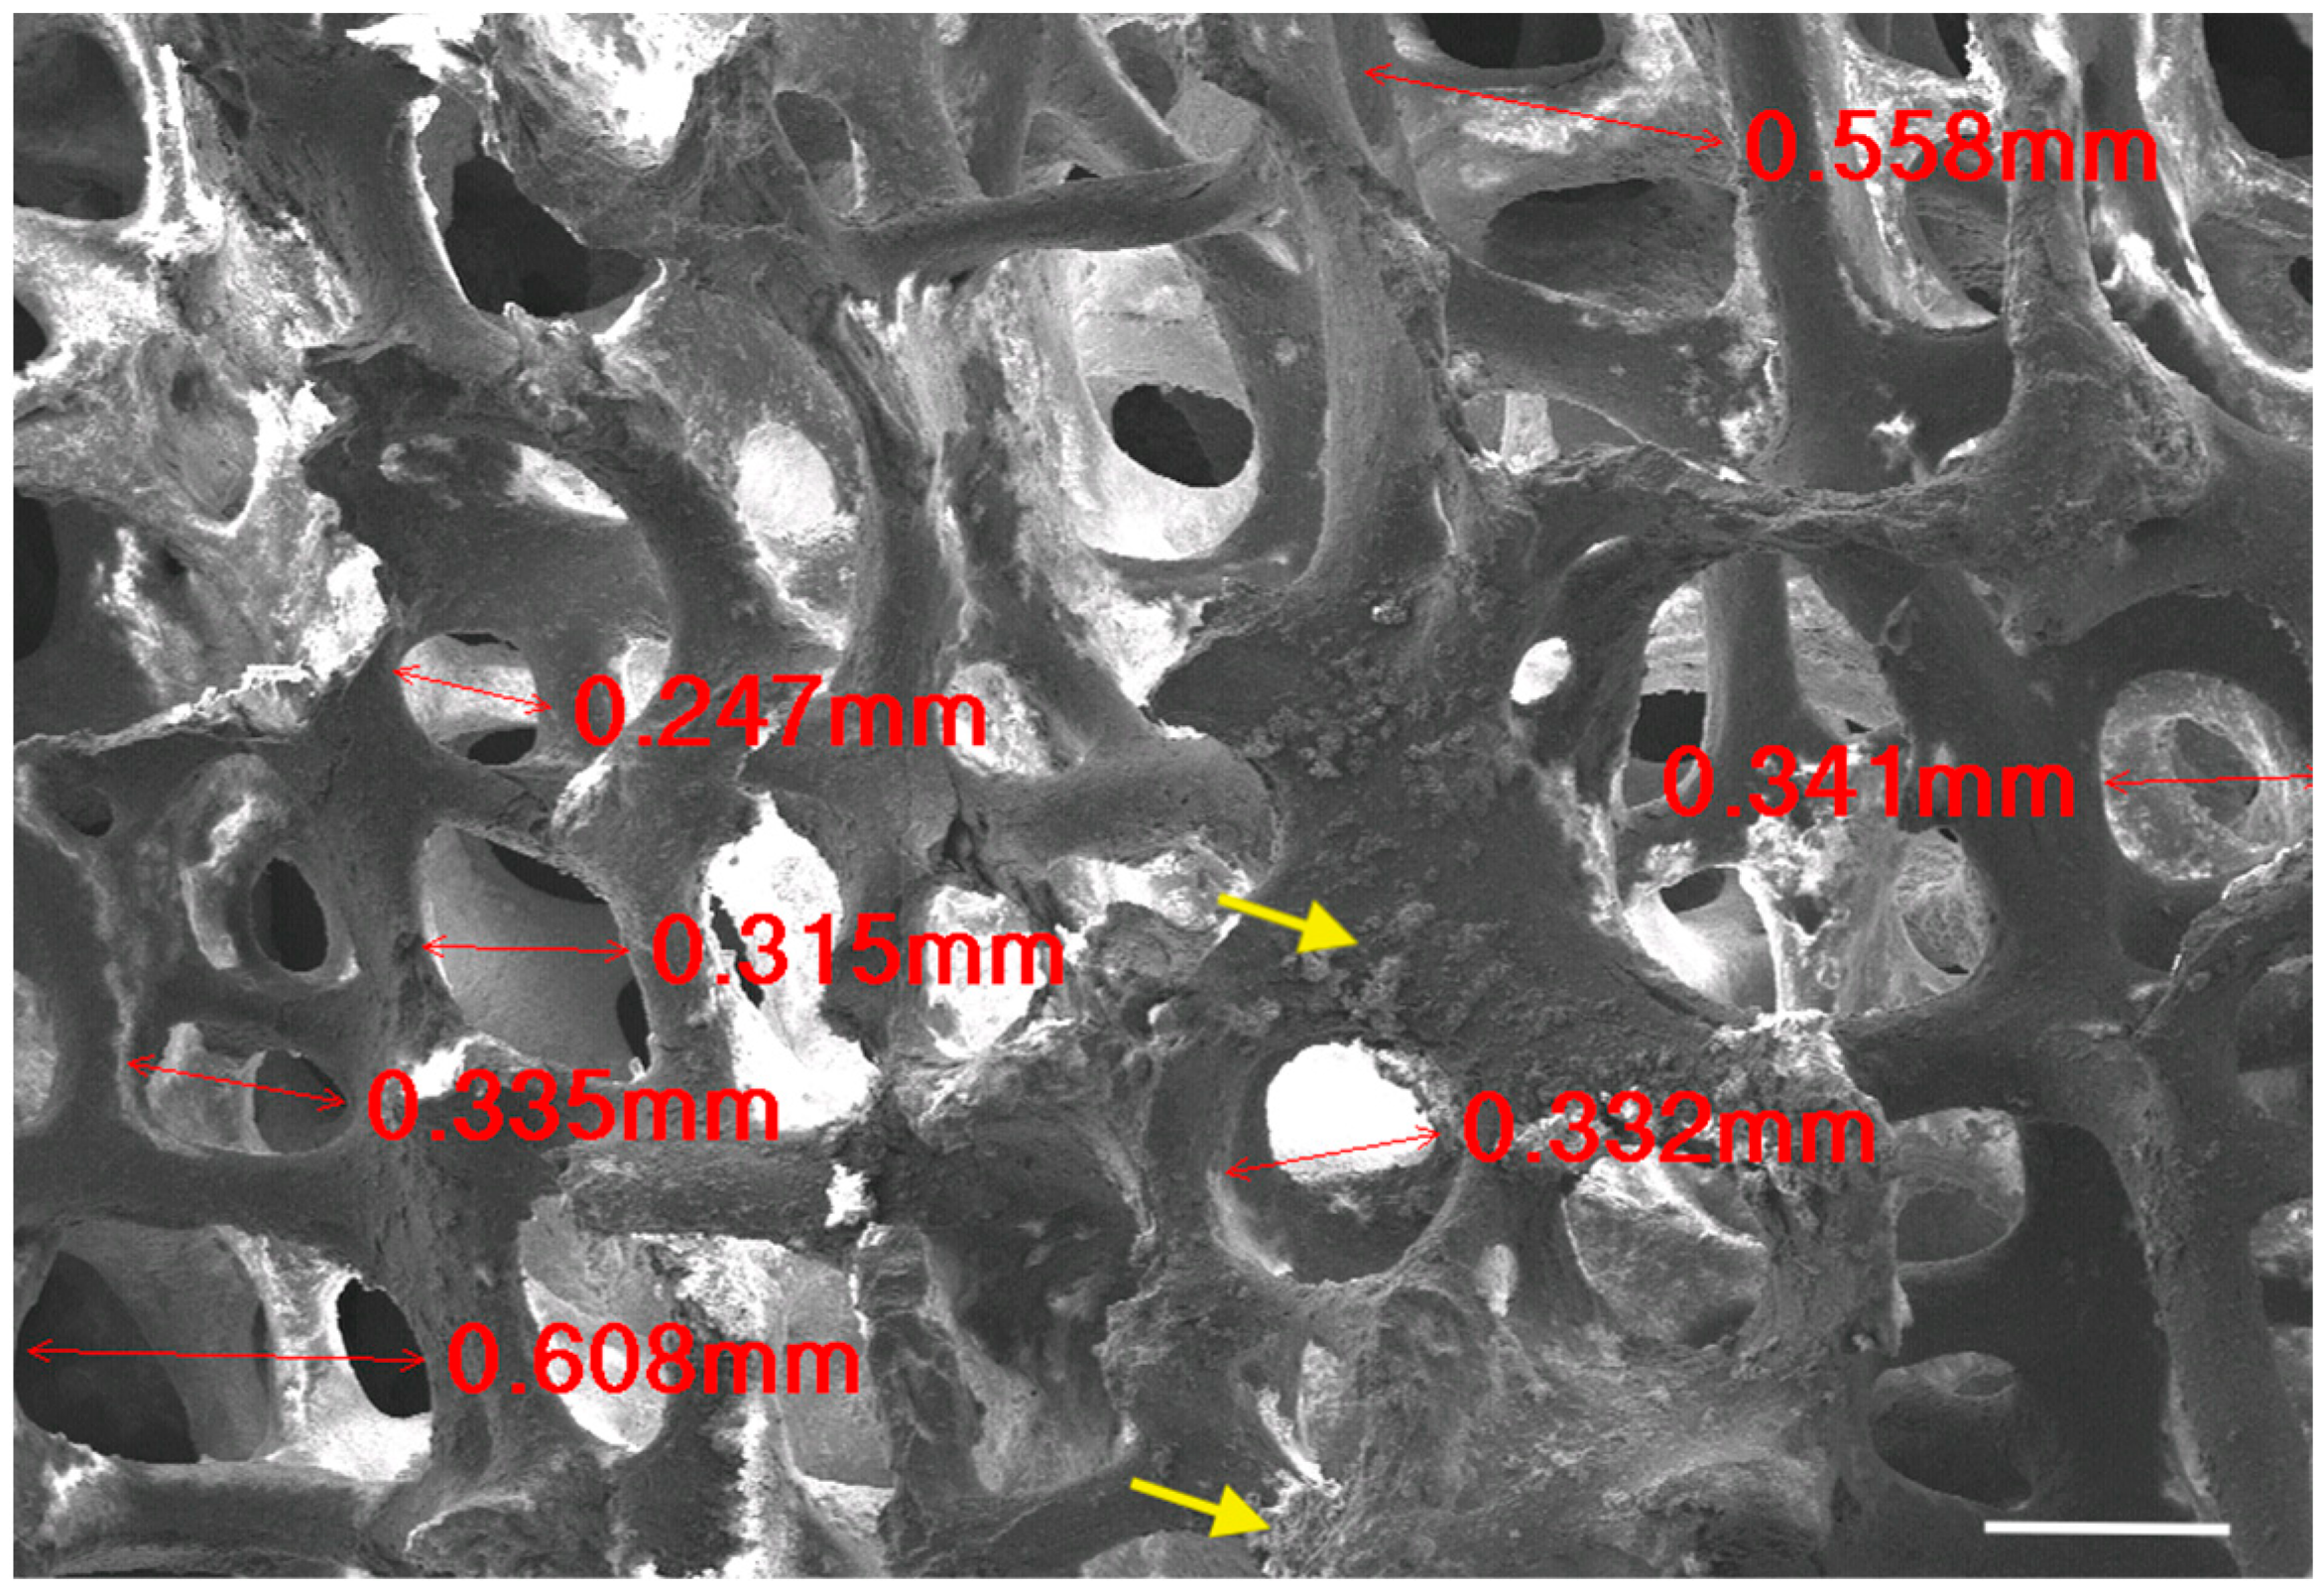

3.1.3. Scanning Electron Microscopy (SEM)